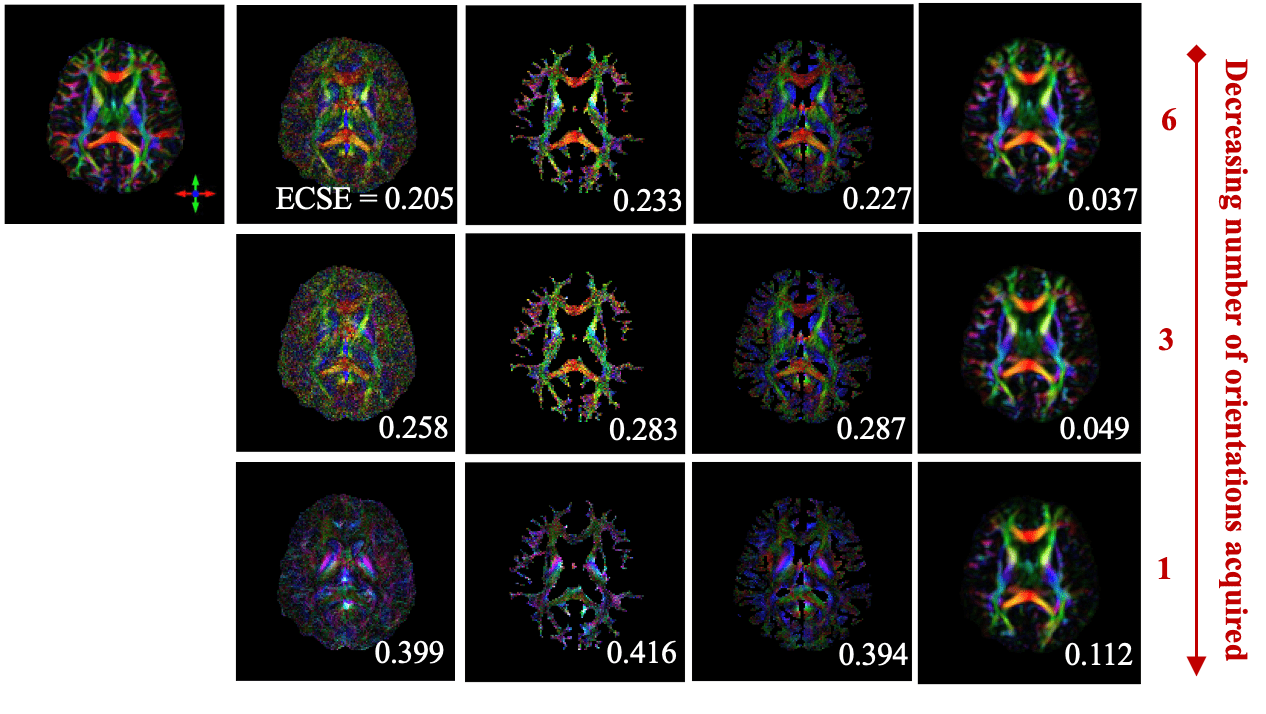

Ground-Truth

STIimag

[Li et al.]

MMSR

[Li and Van Zijl]

aSTI+

[Shi et al.]

DeepSTI

(ours)

Simulation Results

In Vivo Results

DTI